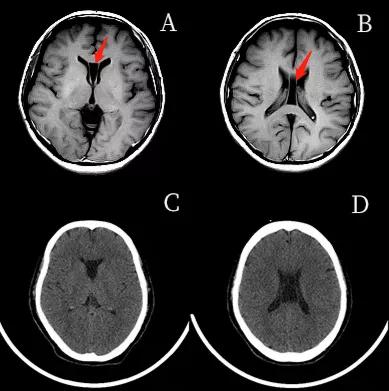

透明隔腔(CSP)的前上方为胼胝体,后下方为穹隆。侧壁即透明隔小叶。透明隔腔≤3mm,描述可见透明隔腔。

1.胼胝体膝部;2.透明隔腔;3.穹隆柱;4.穹隆体;5.穹隆脚;6. Vergae腔;7.胼胝体压部

透明隔腔增宽是透明隔腔≥3mm,直径<10mm,描述可见透明隔腔增宽,透明隔的两壁呈前后平行排列,边界清晰,或内凹,对周围组织无压迫,为正常生理变异,临床无症状。透明隔腔≥10mm,描述可见透明隔腔明显增宽。

两壁呈前后内凹

两壁呈前后平行